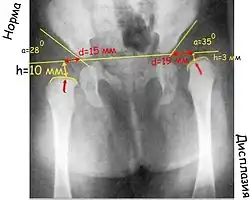

Очень важный показатель, характеризующий дисплазию тазобедренного сустава, — величина h, характеризующая вертикальное смещение головки бедра. Это расстояние от линии Хильгенрейнера до центра головки бедра, то есть примерно до середины видимой на рентгенограмме метаэпифизарной пластинки бедренной кости (на 1–1,5 мм выше).

В норме величина h составляет от 9 до 12 мм. Уменьшение этого размера или различие его справа и слева указывают на дисплазию.

И ещё один важный показатель – величина d – показатель латерального смещения головки бедра относительно вертлужной впадины. Это расстояние от дна вертлужной впадины до линии h. В норме он не превышает 15 мм.